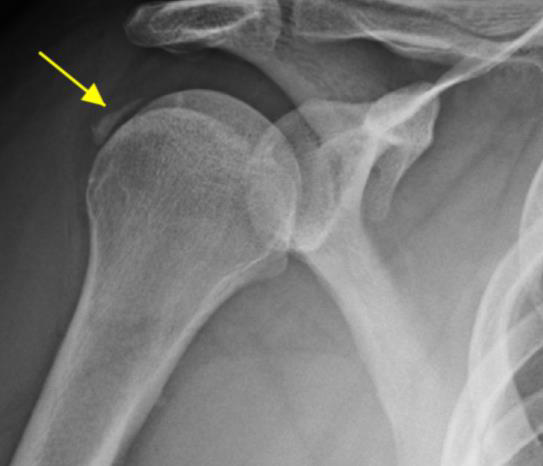

Rotator cuff tear with pain and weakness on exam. There may be catching with overhead movements. This condition is best seen with x-rays of the shoulder. Sometimes an MRI is ordered to rule out a rotator cuff tear.